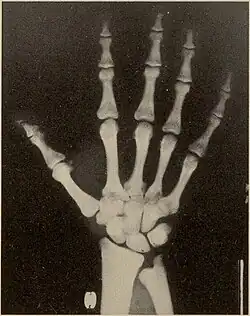

Pycnodysostosis causes the bones to be abnormally dense; the last bones of the fingers (the distal phalanges) to be unusually short; and delays the normal closure of the connections (sutures) of the skull bones in infancy, so that the "soft spot" (fontanelle) on top of the head remains widely open.[9] Because of the bone denseness, those with the syndrome suffer from fractures.[7]

Other abnormalities involve the head and face, teeth, collar bones, skin, and nails. The front and back of the head are prominent. Within the open sutures of the skull, there may be many small bones (called wormian bones). The midface is less full than usual. The nose is prominent. The jaw can be small. The palate is narrow and grooved. There will be delay in fall of milk teeth. The permanent teeth can also be slow to appear. The permanent teeth are commonly irregular and teeth may be missing (hypodontia). The collar bones are often underdeveloped and malformed. The nails are flat, grooved, and dysplastic. High bone density, acro-osteolysis and obtuse mandibular angle are the characteristic radiological findings of this disorder.[10]

Pycnodysostosis also causes problems that may become evident with time. Aside from the broken bones, the distal phalanges and the collar bone can undergo slow progressive deterioration. Vertebral defects may permit the spine to curve laterally resulting in scoliosis. The dental problems often require orthodontic care and cavities are common.

- Hypoplasia or aplasia of the distal phalanges and ribs